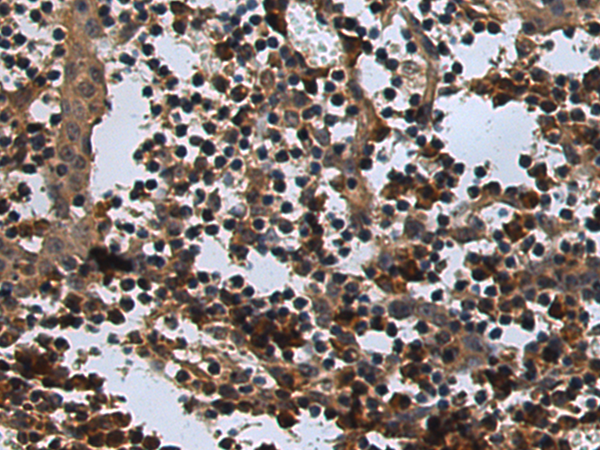

分类: 科研抗体货号: P09472别名:应用: IHC反应种属: Human, Mouse, Rat